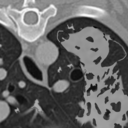

画像診断レポートがどれだけ一般向けの文書でないか、その専門性に気づいてきた方も多いかと思います。 →バックナンバー https://radiologist-rads.hatenablog.com/entry/2019/04/20/173959 今回は、ほぼ気にしなくていいはずの病変(良性)について、レポー…